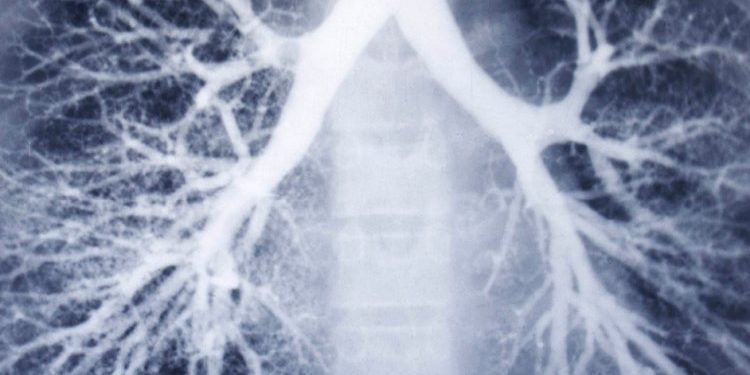

આપણે સૌ જાણીએ છીએ કે, કોરોનાકાળ દરમિયાન ગુજરાતમાં જે લાખો લોકોને કોરોનાની બિમારી સહન કરવી પડી તે પૈકી ઘણાં બધાં દર્દીઓનાં ફેફસાં, કોરોનાથી બહાર આવ્યા પછી પણ અગાઉ જેટલાં મજબૂત અને સ્વસ્થ રહ્યા નથી. આ પ્રકારના ઘણાં લોકો તો આજે પણ પાંચ પંદર પગથિયાનો દાદર ચડે તો શ્વાસની તકલીફોની ફરિયાદ કરતાં હોય છે ! આ સ્થિતિમાં TB મુક્ત ગુજરાતનો સરકારનો જે ટાર્ગેટ છે, તે પાર પાડવામાં અડચણો પેદાં થઈ શકે છે. થઈ રહી છે ! કારણ કે, અન્ય બે કારણો પણ આ દિશામાં નડતરરૂપ જણાઈ રહ્યા છે.

સરકારે અગાઉ એવી જાહેરાત કરી હતી કે, 2025 સુધીમાં ગુજરાતને TBમુકત બનાવવામાં આવશે. અને, સરકાર આ બાબતે ગંભીર પણ છે. દરેક TB દર્દીઓ પર ધ્યાન આપવામાં આવે છે. સતત ફોલોઅપ પણ મેળવવામાં આવે છે. જરૂરી સારવાર પણ ઉપલબ્ધ કરાવવામાં આવે છે. પરંતુ આમ છતાં કોરોનાએ ડેમેજ કરેલાં લોકોનાં ફેફસાં વાયુ પ્રદૂષણ અને ધૂમ્રપાનને કારણે વધુ ડેમેજ થતાં હોવાનું સરકારના ધ્યાનમાં આવ્યું છે.

અત્રે નોંધનીય છે કે, આઠેક વર્ષ પહેલાં સરકારે રાજ્યમાં TB વિભાગમાં જોઈન્ટ ડાયરેક્ટરની જગ્યા જ નાબૂદ કરી નાંખી હતી અને એવો વિશ્વાસ વ્યક્ત કર્યો હતો કે, 2025 પહેલાં રાજ્યમાંથી TB ને ગેટ આઉટ કહી શકાશે. પરંતુ હવે કોરોનાકાળ પછી આ વિશ્વાસ પાલવે તેવો નથી, એવું જણાતાં સરકારે ઉપરોક્ત વિભાગમાં જોઈન્ટ ડાયરેક્ટરની જગ્યા ફરીથી સજીવન કરવી પડી છે ! કારણ કે, આ ફેફસાં ડેમેજ – વધતું જતું વાયુ પ્રદૂષણ અને ધૂમ્રપાન ત્રણેય ચિંતાના વિષયો બન્યા છે.

સરકાર લોકોનાં ખાસ કરીને કોરોના સહન કરી ચૂકેલાં લોકોનાં નબળાં ફેફસાં અંગે ચિંતિત છે. વાયુ પ્રદૂષણ ઘટાડવા પણ ગંભીર છે અને સાથેસાથે ખાસ કરીને યુવાનોમાં ધૂમ્રપાન ઘટાડવા પર જોર ઇચ્છી રહી છે. કેમ કે, ગુજરાતમાંથી TB નાં રોગને દૂર કરવો પણ જરૂરી છે. ગુજરાત દરિયાઈ પટ્ટી મોટી ધરાવે છે તેથી TB નાં કેસો પણ નોંધપાત્ર પ્રમાણમાં જોવા મળે છે. વળી, સૌરાષ્ટ્રમાં ધૂમ્રપાનનું પ્રમાણ પણ વધુ છે.